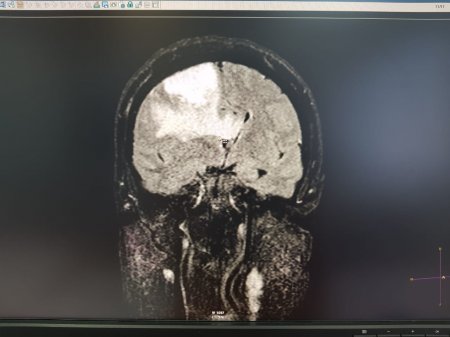

Опухоль мозга диаметром семь сантиметров удалили пенсионерке врачи Мангистау

Дополнительное обследование в аппарате компьютерной томографии (КТ) и магнитно-резонансной томографии (МРТ) показали у пенсионерки наличие отека правого полушария головного мозга.

- Врачи 28 февраля провели операцию по удалению опухоли в правой лобно-теменной области путем костно-пластической трепанации черепа пациентки. Операция прошла успешно, без осложнений, опухоль удалена полностью, - отметили в пресс-службе управления здравоохранения.